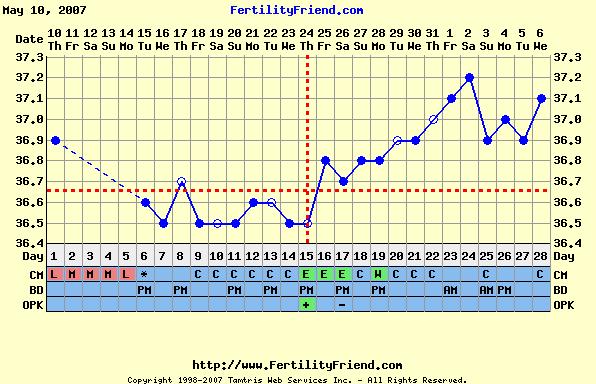

A hőm pedig ilyen, amit már nem értek: